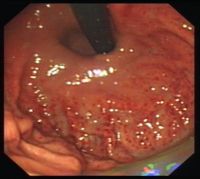

2.慢性萎缩性胃炎根据发病是否与自身免疫有关及是否伴有恶性贫血,分为A、B型;A型属于自身免疫性疾病,患者抗壁细胞抗体(PCA)及抗内因子抗体(IFA)阳性,并伴有恶性贫血,病变主要位于胃体和胃底部;B型多见于胃窦部,无恶性贫血;两者胃粘膜改变相似;胃镜见胃粘膜:由正常的橘红色变为灰色或灰绿色,粘膜层变薄、皱襞变浅甚至消失、粘膜下血管透见,表面有细颗粒、偶见出血糜烂;显微镜可见淋巴细胞、浆细胞浸润、肠上皮化生、腺上皮化生、不典型增生;